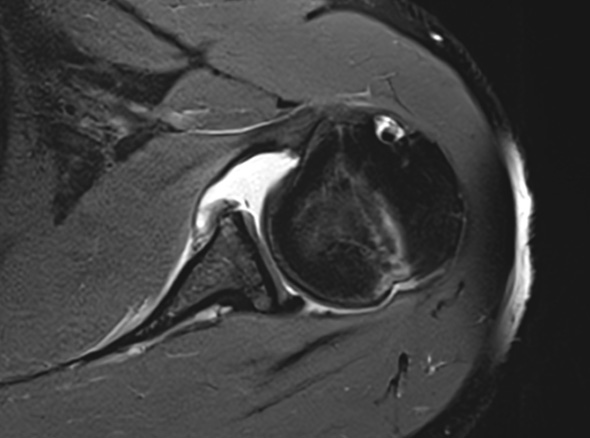

어깨가 가볍게 빠지는 증상, 어깨와 팔꿈치 사이에 있는

상완골이 어깨뼈에서 빠져나오는 증상을 어깨 탈구라고 합니다.

상완골두의 울타리 역할을 하는

관절와순 순상이 동반되는 경우도 있습니다.

관절 내시경을 통해 파열된 관절와순을 정상적인 모양으로 봉합하여 제 기능으로 회복시켜 줍니다.

재발성 탈구(2회 이상)인 경우

첫 탈구이나 관절와순이 전위되어 있어

재탈구 가능성이 높은 경우